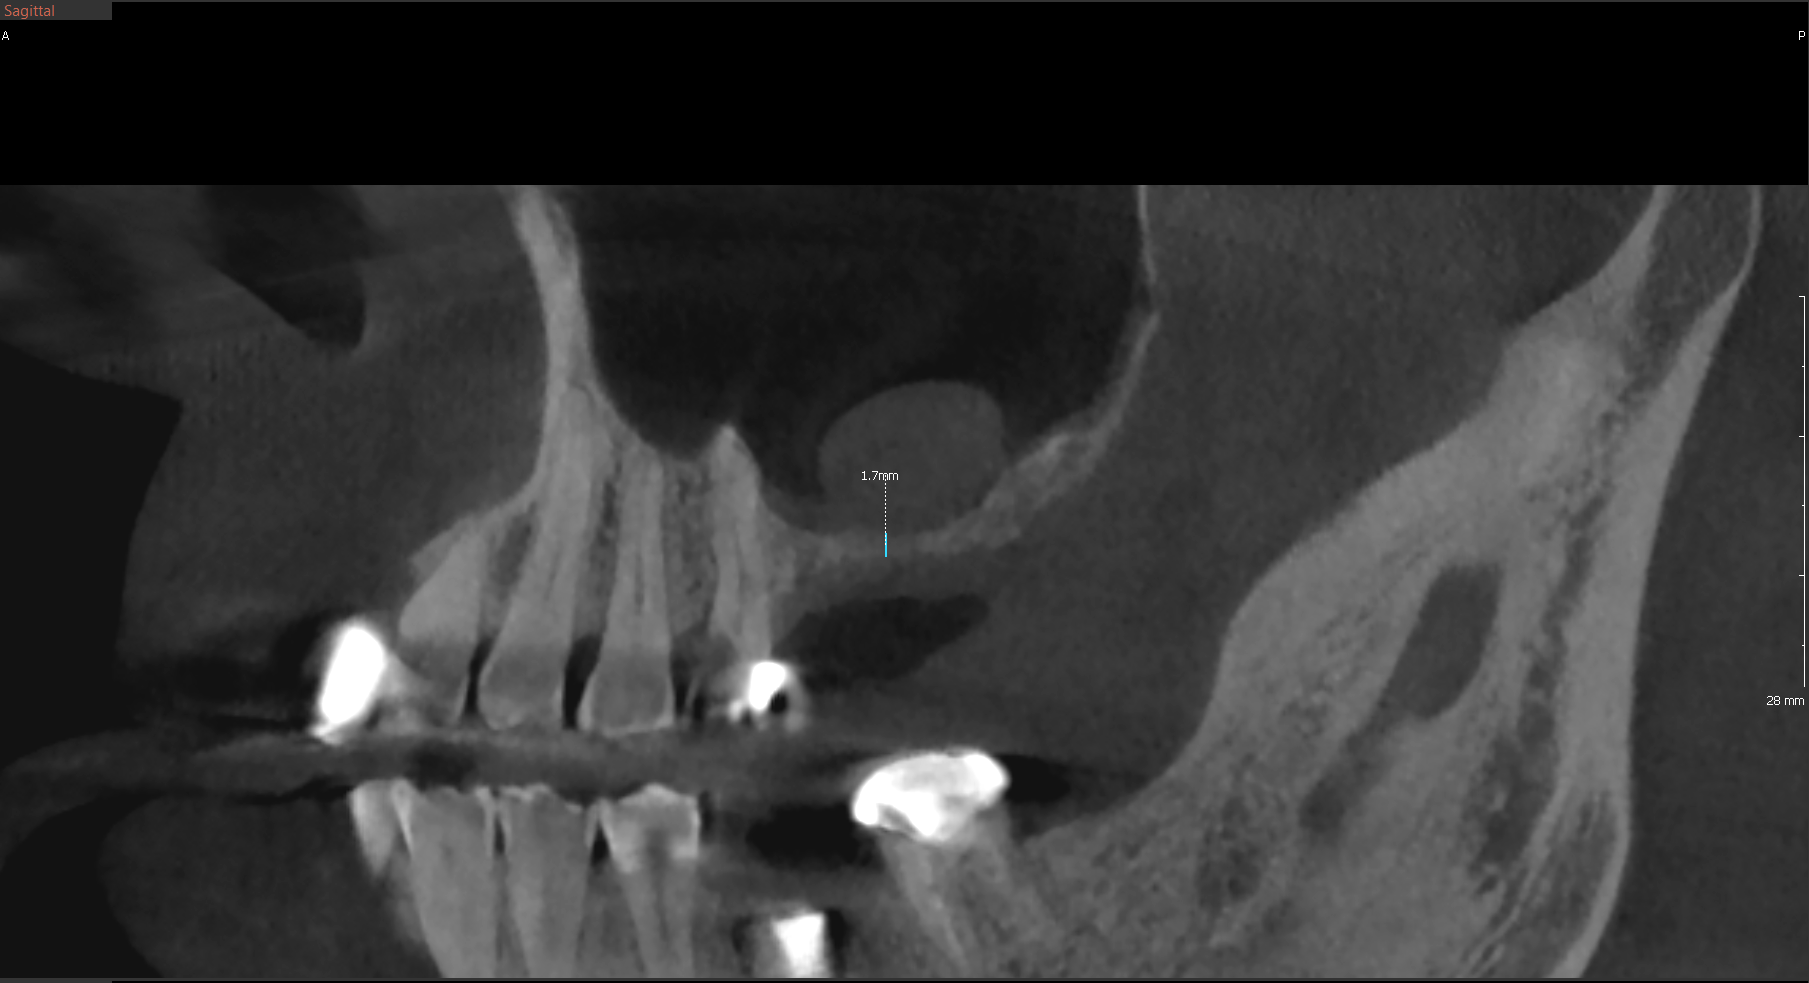

Posterior Maxilla

Challenge: Severe pneumatization of the maxillary sinus leaving only 1.7mm of residual vertical bone height. Insufficient for primary implant stability.

Solution: Lateral window sinus elevation utilizing particulate bone graft and barrier membrane to increase vertical dimension.

Outcome: Vertical bone height increased to 12.5mm. Site successfully regenerated for predictable placement of standard length implants.